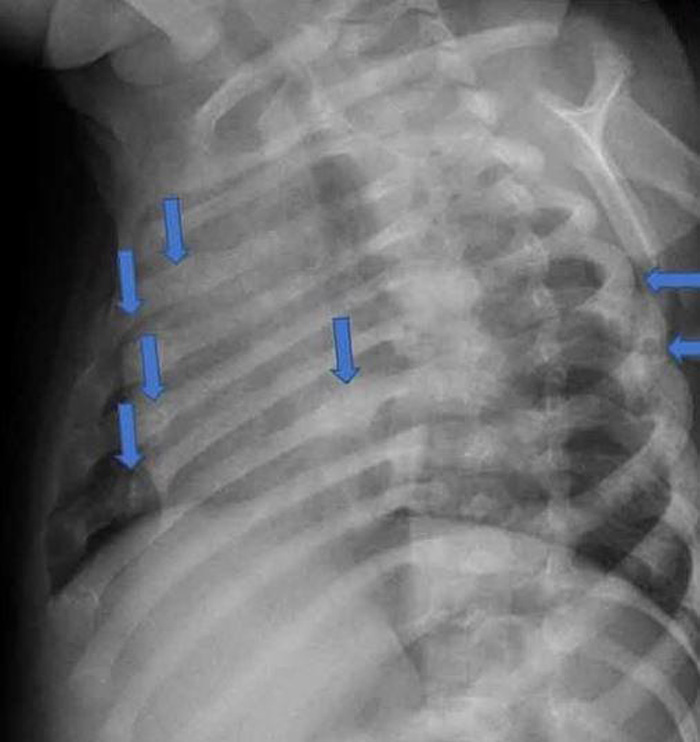

据英国《太阳报》报道,32岁男子建卓札克与22岁妻子柯宾丝卡,在2017年时把年仅4个月大的儿子送到医院,全身是伤。医师检查后认为状况有异,夫妻俩则直呼孩子是被边缘翘起来的地毯绊倒,但医师发现,孩子身上共有28处骨折,而且伤势相当严重,包括手臂、肋骨、膝盖、脚踝等几乎都是全断的状况。医师验伤认为,男婴遭到强大的外力冲击,因此报警处理,建卓札克和柯宾丝卡随后遭到警方逮捕。

肋骨也断了不少处。